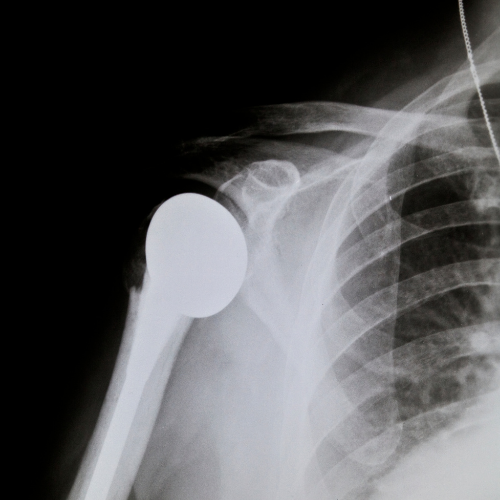

Artroscopia della Spalla e del Ginocchio

L’artroscopia della spalla e del ginocchio è una tecnica chirurgica minimamente invasiva che consente al Dott. Edoardo Cristalli di trattare con precisione diverse problematiche articolari. Questa metodica è particolarmente indicata per risolvere lesioni della cartilagine, lesioni ai legamenti o alla cuffia dei rotatori della spalla e danni alle articolazioni del ginocchio, come le rotture del menisco o dei legamenti crociati. Grazie a piccoli incisions e l’uso di strumenti specializzati, l’artroscopia permette un recupero rapido, con un minor dolore post-operatorio e un ritorno veloce alle normali attività.